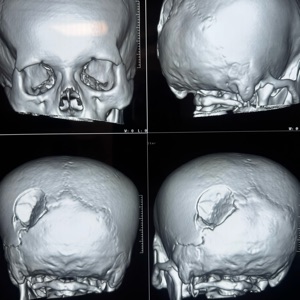

Surgical management of traumatic brain injuries (TBI) focuses on pressure relief, bleeding control, and repair of fractures. Strategies may include craniotomies to remove hematomas or relieve intracranial pressure, debridement of damaged tissue, and stabilization of skull fractures. The surgery aims to prevent further brain injury and address life-threatening conditions, with rehabilitation often following.